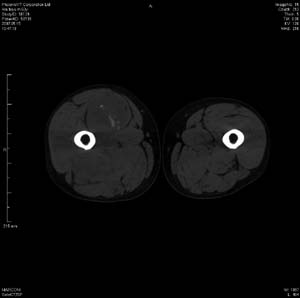

男 63岁 右大腿无痛性肿块11年,x片右大腿软组织肿块影,余无明显异常.ct值-13__239hu

右大腿股内侧股与收肌间隙间多发囊实性占位,界清.内示斑点状钙化.局部骨质无异常.肌肉推压移位表现.

考虑肌间隙病变.可有1,神经来源肿瘤.2,血管来源病变.3,淋巴来源肿瘤.4,脂肪来源肿瘤.5,滑膜来源肿瘤.结合病史只能考虑良性占位.建议增强或mri进一步分析.

同意,病史较长,病变周围分界清晰,考虑良性病变。病灶内有多发斑点状钙化,沿肌间隙生长,血管瘤或淋巴管瘤首先考虑。